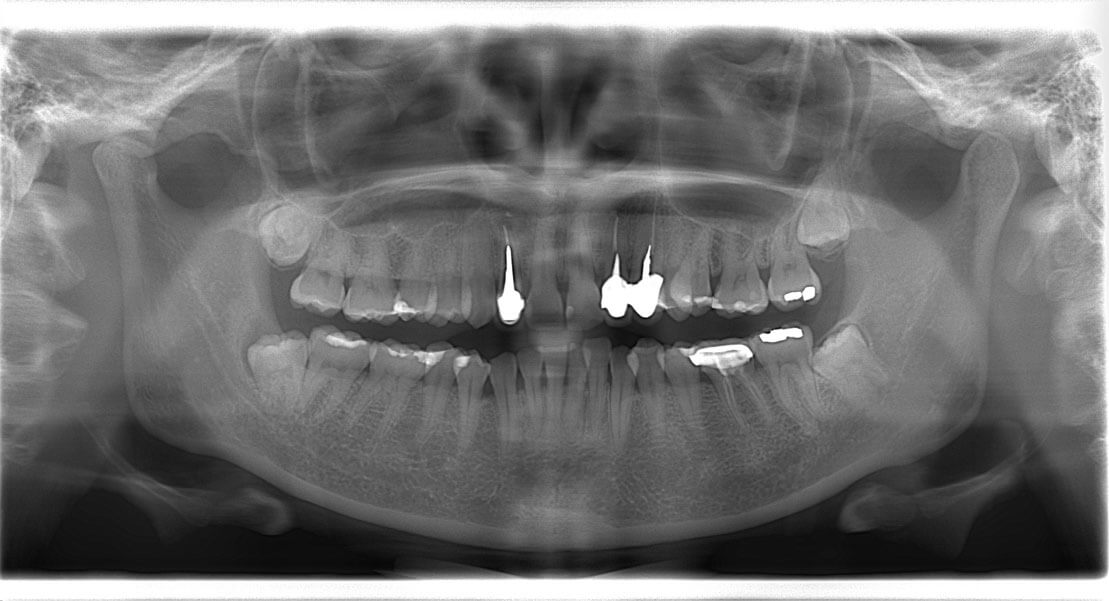

首先在植牙手術前,我們會做詳細的評估,這包括身體的健康狀況,口腔清潔,植牙部位的條件,有任何其他咬合的問題等。這時會先拍攝環口X光片與 3D斷層影像CT,來評估牙肉底下的骨頭條件。

我們的口腔組織不是平面而是3D立體的,許多的組織構造是無法靠一張平面的X光片就可以看得淸楚,所以 3D斷層影像CT 就很重要。透過斷層掃描CT的資訊,可以讓我們看到臉部許多組織構造的3D位置,在手術時就可精準的避開重要的神經與血管,進而增加植牙手術的安全性。